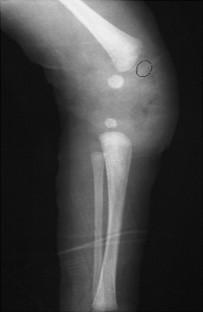

Neonatal physeal fracture of the distal femur is often difficult to diagnose. Timely and accurate diagnosis and appropriate therapy are critical in order to avoid permanent morbidity and dysfunction of the affected limb. We describe an infant in whom closed reduction and pinning were required in order to assure a good outcome.